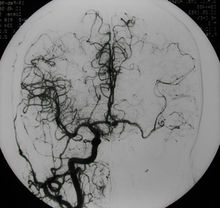

DSA即血管造影的影像通过数字化处理,把不需要的组织影像删除掉,只保留血管影像,这种技术叫......>>详细